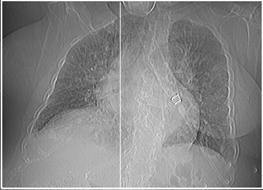

*Pulmonary CT angiography: No signs of PTE. Signs of PHT. Signs of hemodynamic decompensation with probable perihilar cardiogenic edema, bilateral pleural effusion and cardiomegaly (Figures 5 and 6).

Figure 5 Cardiomegaly. Bilateral pleural effusion.

Figure 6 No signs of PE.